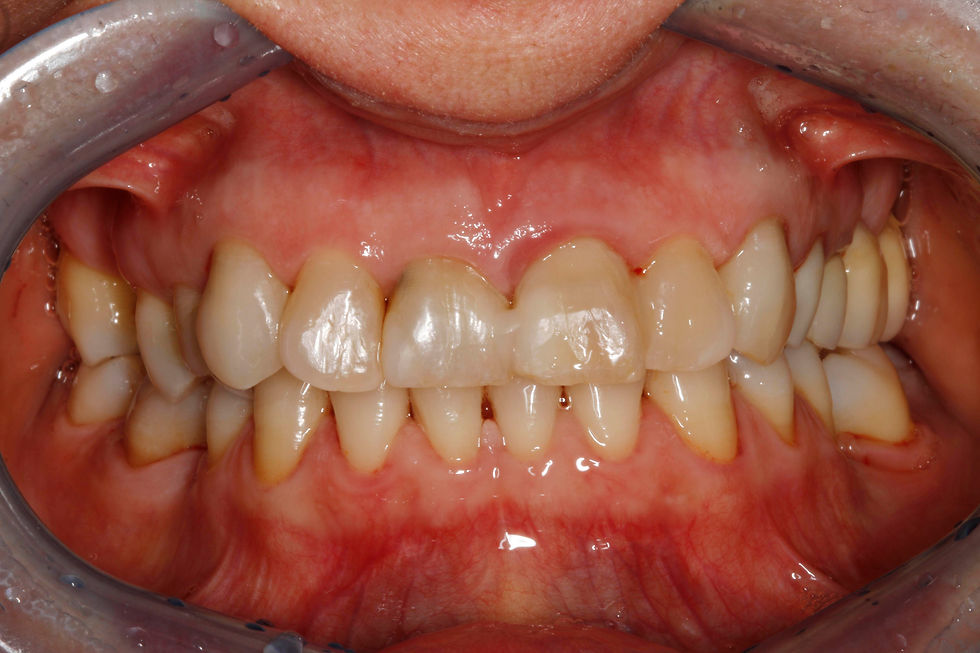

Clinical image and initial radiograph: the fractured on the element 2.1 is noted.